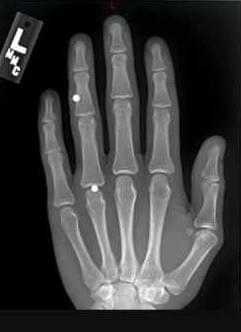

Заподозрить присутствие ИТ возможно с помощью визуального осмотра и пальпации. В особых случаях назначается рентгенодиагностика, которая включает рентгенографию, рентгеноскопию, электрорентгенографию. Все ИТ классифицируются как рентген контрастные - видимые на снимке при рентгенографии, малоконтрастные - трудно определяемые на рентгеновском снимке, и рентген неконтрастные - не проявляющиеся при рентгенографии. Последние могут быть выявлены с помощью ультразвукового исследования.

Обнаружить и уточнить расположение контрастных инородных тел при рентгенологическом исследовании значительно проще, чем распознать неконтрастные тела, внедрившиеся в ткани. Рентгенография кисти обязательна как в том, так и в другом случае, так как иногда удается уловить на пленке легкую тень и от рыбьей кости, и от стекла или деревянной занозы. Предложено много различных способов уточнения локализации инородных тел, но для кисти наиболее простыми и надежными являются рентгенография в трех проекциях и рентгеноскопия. При этом отыскивается точка наибольшего погружения инородного тела при надавливании, подводится к инородному телу стерильная игла, и тогда определяется удобный доступ. Поэтому при рентгенографии всегда рекомендуется присутствие хирурга. Прямой снимок делается в положении кисти, соответствующем тому, какое она будет иметь на операционном столе; второй снимок — в строго боковой проекции, он дает представление о глубине залегания инородного тела.

Инородные тела чаще задерживаются в пясти — 47 %, затем в пальцах — 36,8%, реже в запястье — 10,1 %. Изредка, главным образом при огнестрельных ранениях, они бывают рассеяны по всей кисти — 2,5%, и в 3,6% локализация не уточнена. Большинство хирургов считают, что не все инородные тела сразу подлежат удалению. Исключение составляют лишь графит, кусочки краски, подлежащие удалению из-за опасности вызываемого ими некроза тканей.